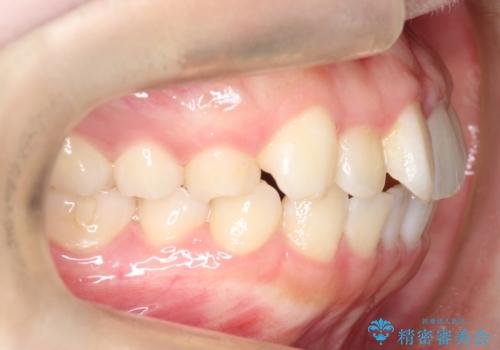

【インビザライン】前歯の凸凹をなおしたい

- 前歯のガタガタを主訴に来院されました。

インビザラインで綺麗な歯並びになり、患者さんには大変満足していただきました。

インビザラインは軽度叢生治療において優れた選択肢となります。